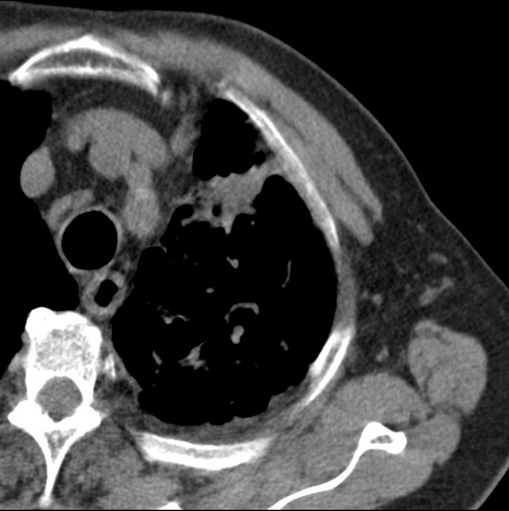

标题: CT25434:胸部CT增强扫描

男性患者 81岁 咳嗽 咳痰 咯血

肿块贴近左肺门,包绕左上肺动脉,形态不规则。肿块增强扫描中度强化。纵膈内主动脉弓左旁间隙、气管隆突前、下间隙见多枚淋巴结影。综上考虑左侧中央型肺癌可能性大。图片没有完整上传,尤其是左肺上叶支气管分支层面没有上传,因此不好判断是叶支气管中断还是段支气管中断。另外,下图红色部分所示是“黏液支气管征”吗?